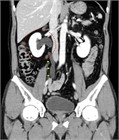

1. 片側の腰背部痛や側腹部痛では水腎症を念頭に置き、まず超音波検査を行い、尿路閉塞の位置と原因を同定するには単純CTを撮影する。